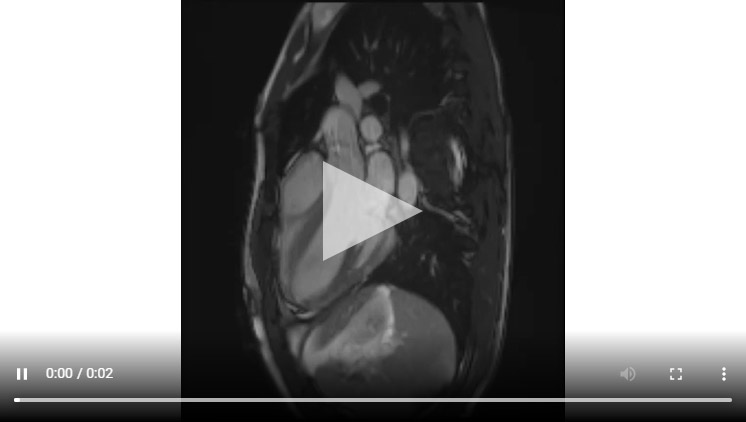

Figure 1B : Séquence Ciné-IRM coupe 3 cavités